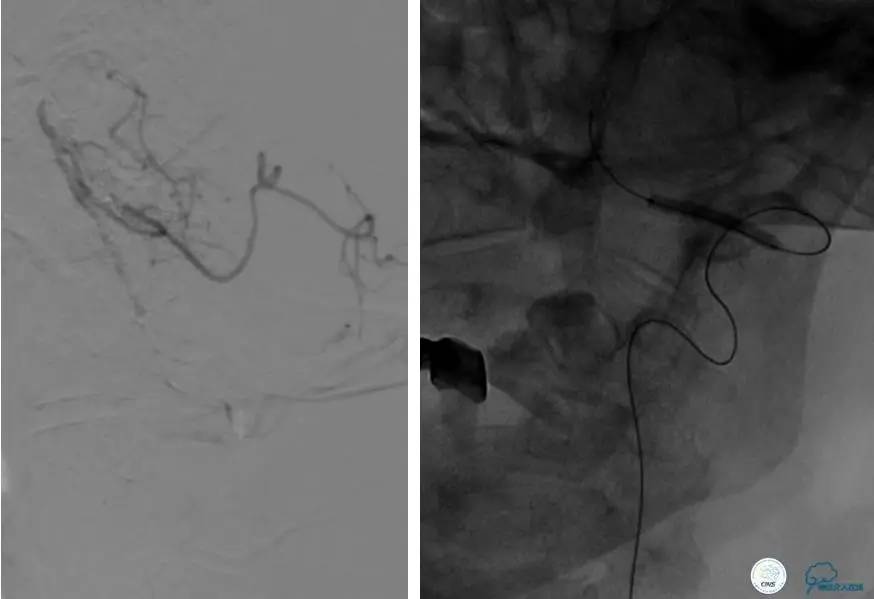

患者:49岁男性,左侧偏瘫1个月,药物治疗、康复训练效果不好,转我院,肌力0~1级。

core-clilnical明显不匹配,是介入开通的合适患者。

造影评价血管、判断闭塞段,微导丝谨慎穿过闭塞段,微导管造影,交换技术,球囊扩张,Enterprise支架。在后扩张时导丝刺破M3段血管,蛛网膜下腔出血(SAH)。

微导管进入破裂血管,栓塞弹簧圈1枚,出血停止,结束手术。继续双抗,术后2天肌力2级,神经功能恢复明显加快。

术后即刻和6天后CT,患者无明显临床症状。

半年后复查造影,无支架内再狭窄,可见弹簧圈,患者恢复至自己柱杖行走。